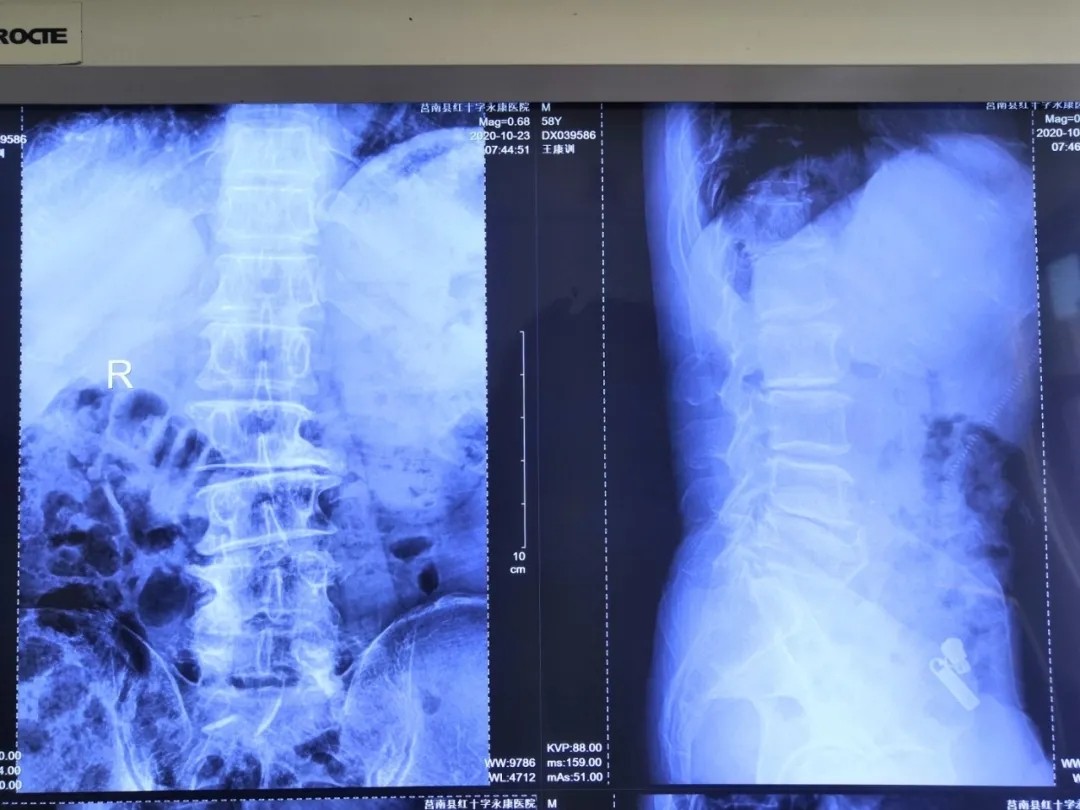

术后影像: